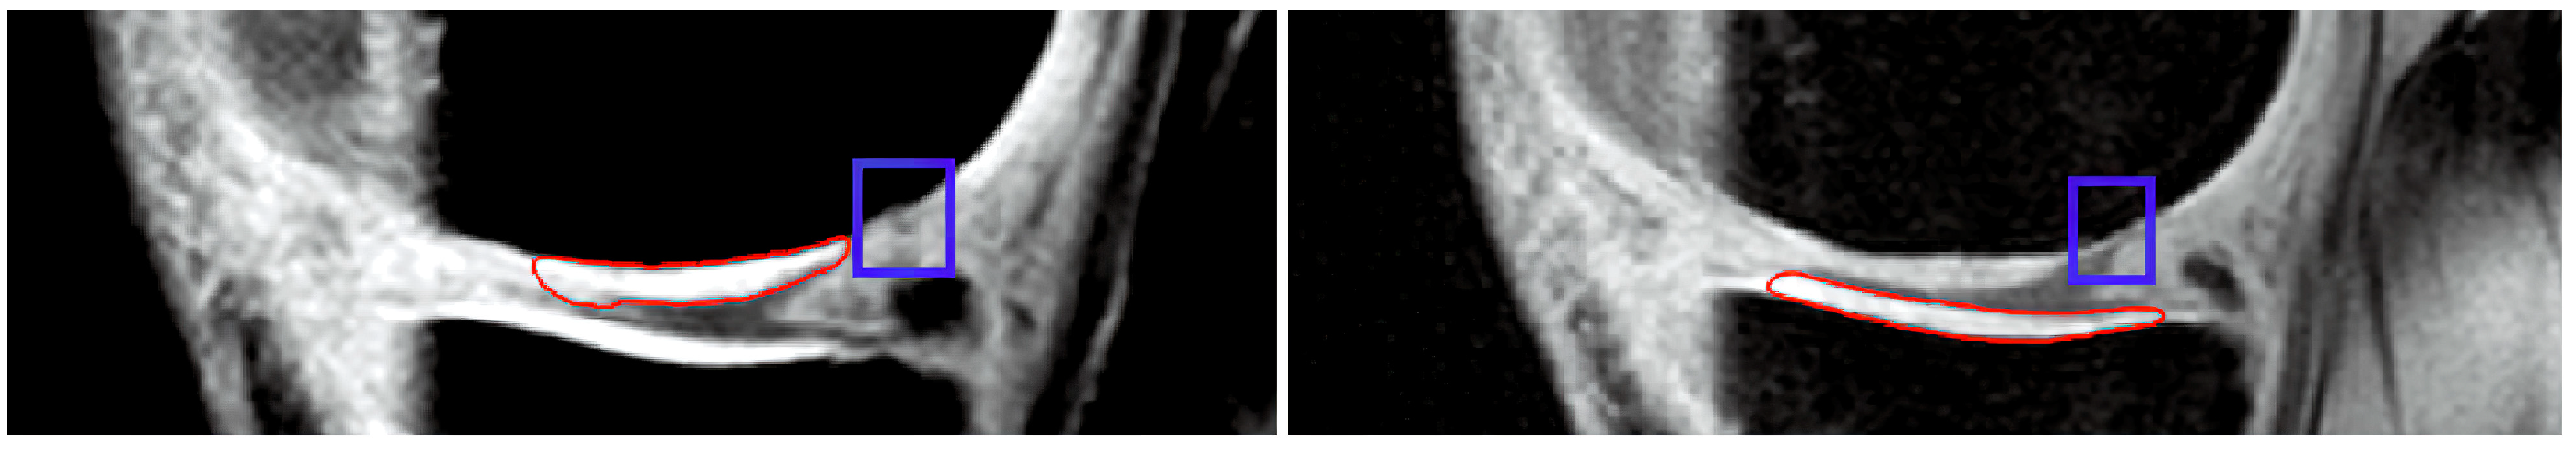

This section brings the most interesting results for the clinical evaluation of articular cartilage as a classification of early signs of osteoarthritis, which manifest as cartilage loss. This is substantially important to distinguish these cartilage features from those of healthy cartilage with compact structure, which is usually represented by a homogenous MR signal. On the other hand, cartilage loss is standardly represented by intensity variations and a weaker MR signal when compared with healthy cartilage (Figure 12). In order to classify such early signs of cartilage loss from the healthy cartilage structure, we used two convolutional neural networks (CNNs): GoogLeNet and ResNet 18, with various hyperparameter settings to find the best alternative for the cartilage loss classification. For this classification, we used the segmentation data of articular cartilage based on the proposed clustering scheme with a genetic algorithm. This alternative is used due to its best performance, as we declared in the previous section. We performed segmentation for 1000 MR images in total, which were equally divided into 500 healthy images and 500 images with early cartilage loss. As an example of the segmentation based on the genetic algorithm-based clustering, we show the closed segmentation curve, which outlines a part of the cartilage area (healthy cartilage) where other parts of the segmentation model are eliminated.

Figure 12. Examples of detection tibial (left) and femoral (right) articular cartilage by GA-based clustering, where the blue squares indicate the spots of early cartilage loss.